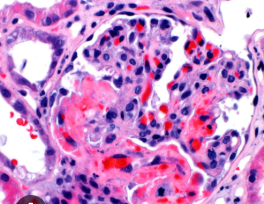

용혈요독 증후군은 대체로 장출혈성 대장균(O157:H7)이나 이질균, 살모넬라균 등에 오염된 음식 섭취로 발생합니다. 세균이 장벽에서 독소(Shiga toxin)를 생성해 혈관 내피를 손상시키며, 이로 인해 적혈구가 파괴되고 신장 내 모세혈관에 혈전이 형성됩니다. 비전형적 HUS는 유전적 결함, 면역억제제 사용, 폐렴구균 감염 등 다양한 원인에서 비롯될 수 있습니다. 특히 여름철 위생 관리 소홀 시 발생 위험이 높습니다. 안전한 조리와 식품 관리가 예방법의 핵심입니다.

이 질환은 급성 신부전과 함께 나타나며, 피 섞인 설사, 구토, 복통 등의 장염 증상으로 시작됩니다. 이후 혈소판이 감소해 멍이 잘 들거나 코피가 나는 증상이 생기고, 창백함과 피로감이 동반됩니다. 소변량 감소나 부종, 혈압 상승은 신장 손상 징후입니다. 심한 경우 신경계 합병증이나 심장 손상으로 이어질 수 있습니다. 조기에 발견하면 대부분 회복이 가능하지만, 치료 지연 시 생명이 위험할 수 있습니다.